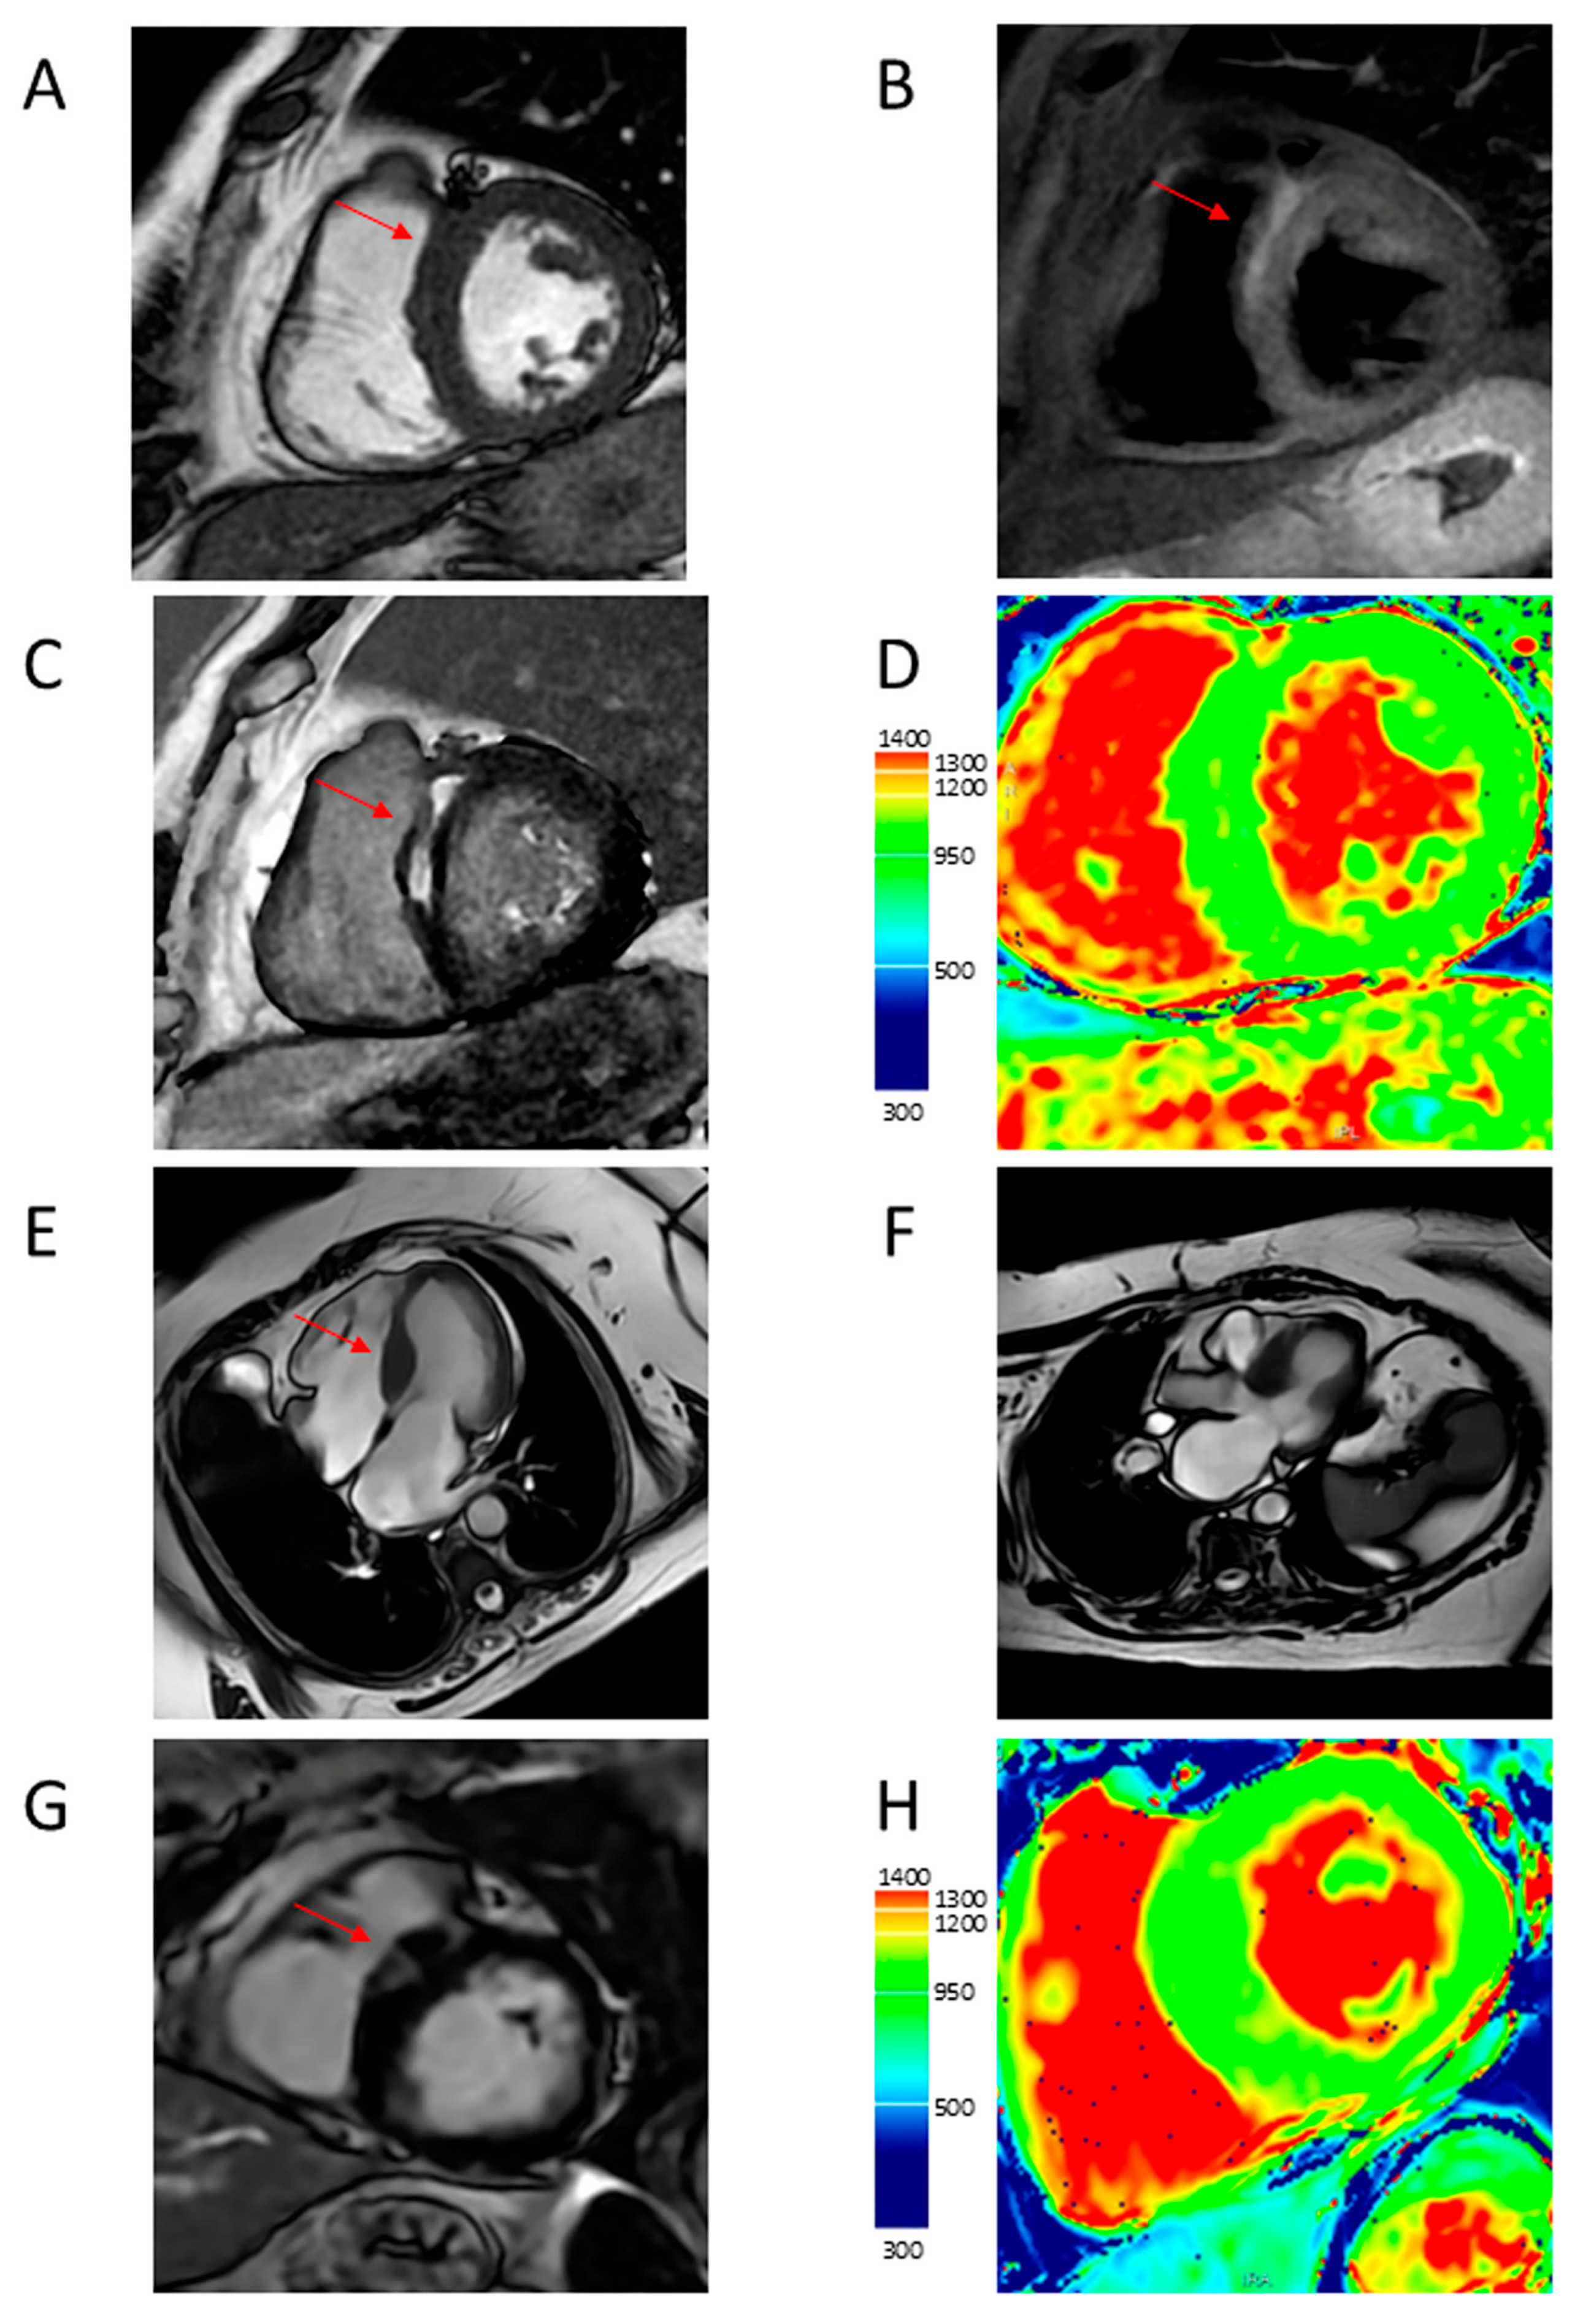

4.1. LV Hypertrophy

4.2. Apical Aneurysm

4.5. Myocardial Fibrosis

4.6. Microvascular Dysfunction